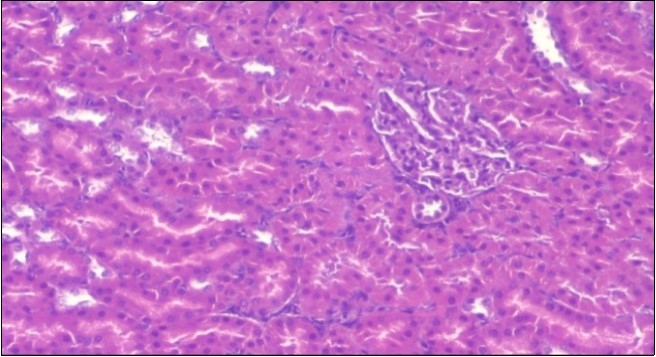

Effect of Ator, Fennel and Their Combination on the Histology of the kidney of the Obese Rats

The histological examination of the kidney of the control rats fed on a standard diet showing normal rounded capsules with normal Bowman's glomeruli, round proximal tubules and elongated distal tubules with high cuboidal cells figure 1. The rats fed (HFD) showed fatty degeneration of the tubules with eosinophilic material deposition, glomerular atrophy with wide urinary space and distal tubules with extrusion of nuclei into lumen figure 2. By comparison kidneys of rats which were treated by fennel after being obese and the control rats observed partial improvement in both Bowman's capsules and proximal tubules. Note the distal tubules show less focal fatty infiltration figure 3.While examination of rats kidney that were treated by ator after obesity showed improvement in Bowman's capsules with normal glomerular and partial improvement in proximal tubules and distal tubules, figure 4. Kidney of rats that were treated by fennel and ator after obesity and the control rats showed high improvement in the tissues with normal glomerular and that Most of Bowman's capsules and renal tubules, restoring their normal appearance figure 5.

Figure 1.Photomicrogragh of kidney section of control rat showing normal rounded capsules with normal Bowman,s glomeruli, round proximal tubules and elongated distal tubules with high cuboidal cells , (H&E) (40X).

Figure 2.Photomicrogragh of kidney section of obese rat showing fatty degeneration of the tubules with eosinophilic matrial deposition, glomrerular atrophy with wide urinary space and distal tubules with extrusion of nuclei into lumen , (H&E) (40X).